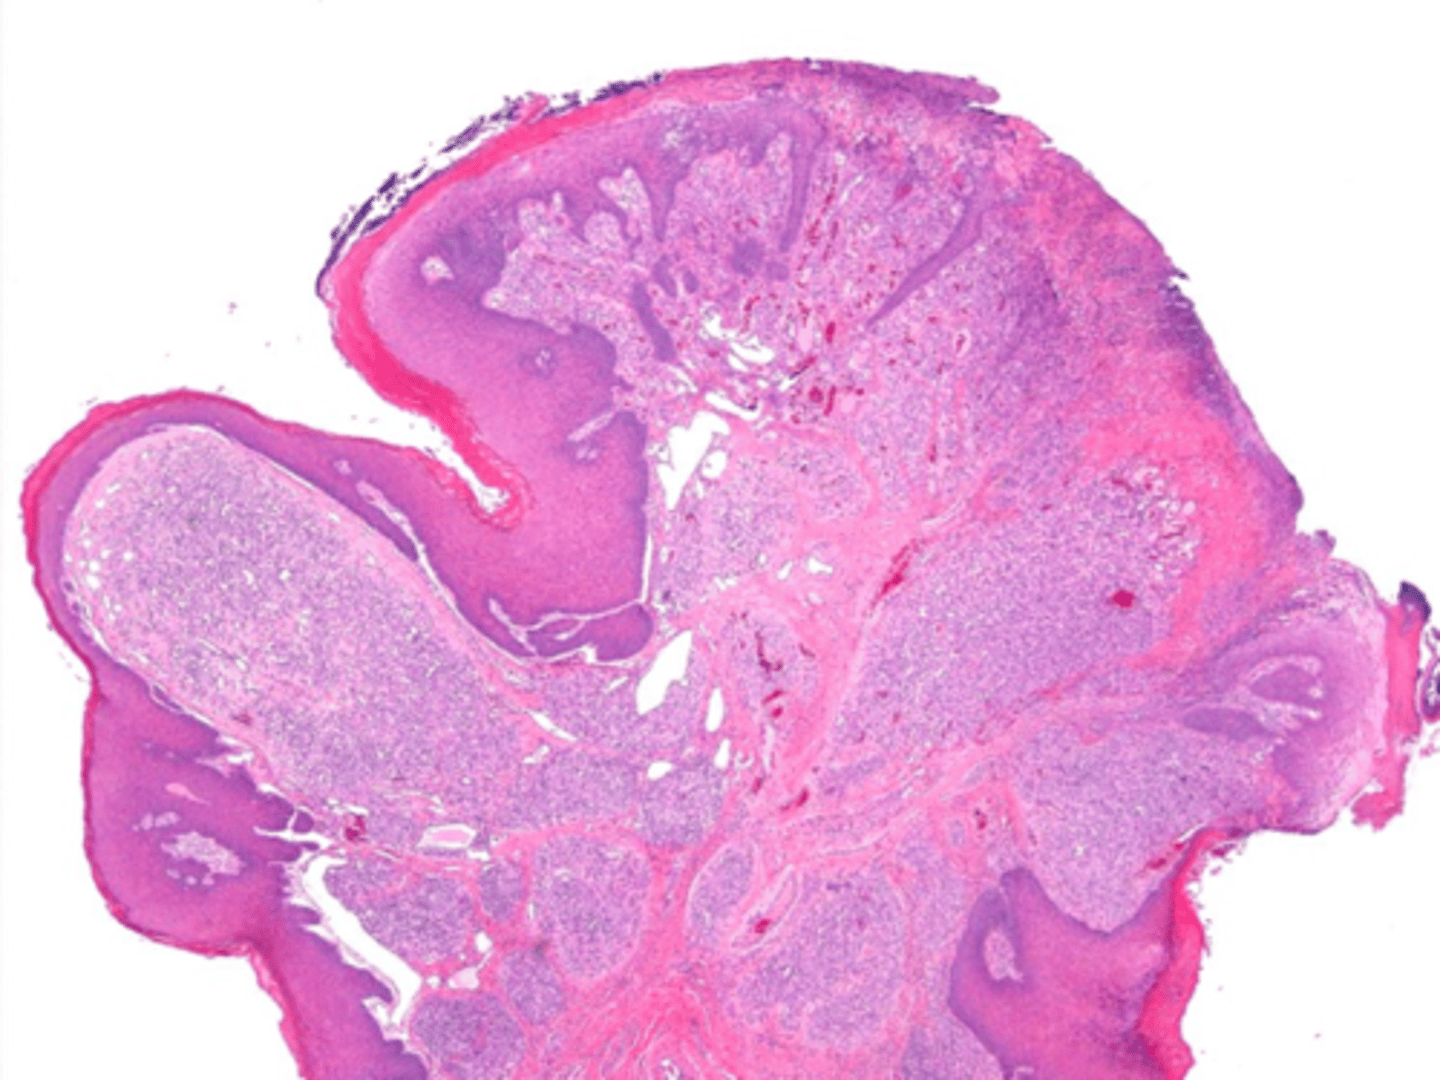

Giant Cell Fibroma

patient presents with an asymptomatic nodule with papillary surface on the anterior dorsal tongue. Histopathologic features show vascular fibrous connective tissue , numerous large stellate fibroblasts that contain several nuclei and rete ridges narrow and elongated. What do you suspect?

Giant Cell Fibroma

vascular fibrous connective tissue , numerous large stellate fibroblasts that contain several nuclei and rete ridges narrow and elongated. This is associated with what pathology?

conservative excision

treatment for Giant Cell Fibromas: